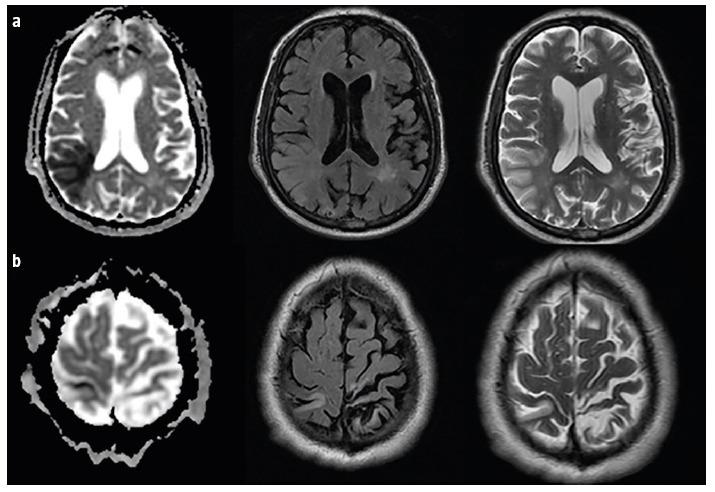

Four patients presented after sudden-onset gait lateropulsion. On neurological examination, all patients had at least one cortical sensory deficit and wide-based gait with lateropulsion towards the side of the cortical deficit. Neuroimaging revealed a subacute parietal lobe stroke contralateral to the side of gait lateropulsion. In two patients we found bilateral lateropulsion with predominance towards the side of cortical deficit and increase of unsteadiness with eye closure (an apparent Romberg sign), with neuroimaging revealing bilateral parietal strokes (subacute contralateral and chronic ipsilateral to gait lateropulsion).

4 例患者出现突发性步态侧方偏倚。在神经学检查中,所有患者均至少存在一处皮质感觉缺失和宽基底步态,并伴有向皮质缺失侧的侧方偏倚。神经影像学显示与步态侧方偏倚侧相对应的亚急性顶叶中风。在 2 例患者中,我们发现双侧侧方偏倚,以皮质缺失侧为主,并伴有闭眼时不稳定性增加(明显的 Romberg 征),神经影像学显示双侧顶叶中风(亚急性对侧和慢性同侧与步态侧方偏倚)。